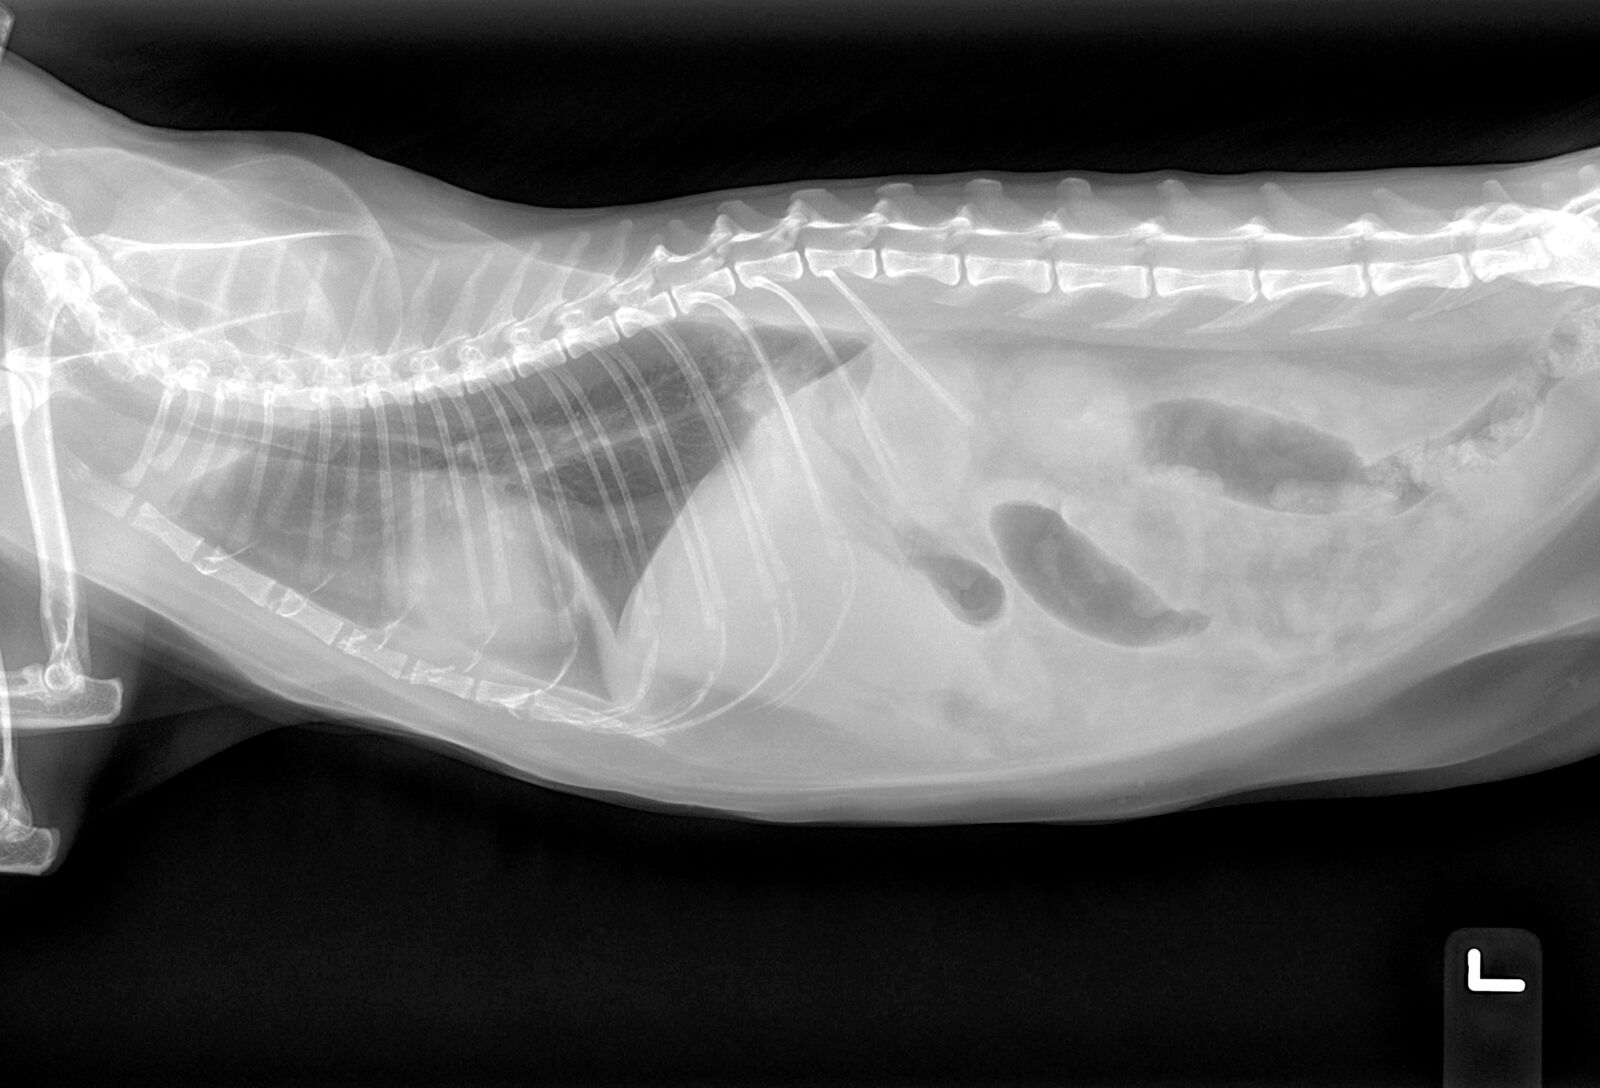

Ascites pronounced a-site-eez is the accumulation of fluid in a cats abdominal cavity.

. Ascites pronounced a-site-eez is the accumulation of fluid in a cats abdominal cavity. The reason that it leads to ascites is because the cats heart is struggling to distribute blood throughout its body and the symptom of swelling appears also in the cats. The diagnosis of a neoplasm is based on.

Pain in the affected joint or joints. In cats with ascites an abdominal swelling is commonly noticed. SEPTIC peritonitis is a diagnosis that results in many clinicians groaning internally.